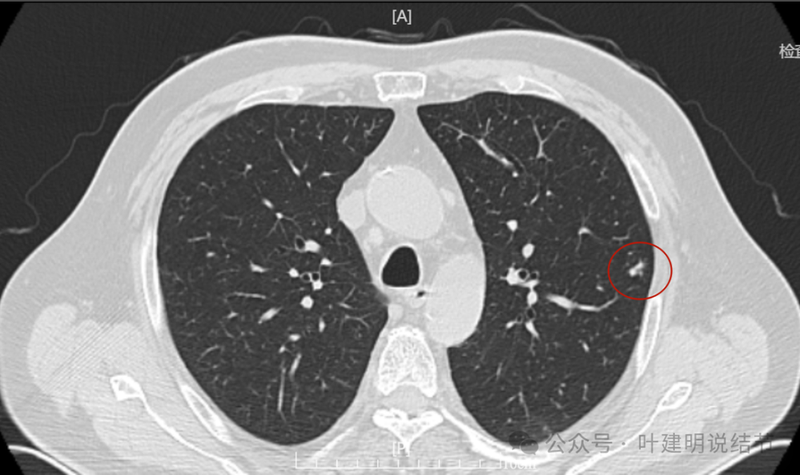

右上叶另有实性结节,密度较高,边缘略显糊。

回顾2023年右侧纵隔肿大淋巴结也是有的,而且大小与2024年9月的相仿。

我想我们这样来考虑问题:1、左肺上叶主病灶实性密度、随访持续进展,边缘有血管穿过并形成血管弯征,这种病灶要警惕是恶性的;2、位置在胸膜比较近的地方,单孔胸腔镜下局部切除方便,即便真的是肉芽肿性炎或者良性,手术创伤以及切除的肺组织并不多,但是却可以去除病灶并明确诊断;你赌他是良性,但如果事实上是恶性,实性密度的随访会延误病情。而切除即便良性也是利大于弊;3、左肺上叶这个病灶本身没有结核的典型表现,整体轮廓比较清楚,没有卫星灶,也没有边缘偏模糊的情况,影像上并不是很考虑是结核或者是肉芽肿性炎。虽然肉芽肿性炎也确实有随访进展的,但我们要从风险高低的角度来考虑;4、右侧腔静脉旁以及龙头下都有肿大淋巴结,左侧主动脉弓下也有肿大淋巴结。当时左肺上叶病灶非常微小的时候,淋巴结肿大已经存在。而且对比淋巴结没有进一步增大,左侧这个病灶却持续进展。这用一元论不能够解释,如果淋巴结肿大是反应性增生或者肉芽肿性炎症,和左侧主病灶是肿瘤性质的,那么就非常能够解释这样的现象。所以你这个病灶我的意见是建议胸腔镜下微创切除。先做楔形切除,如果良性结束手术,如果恶性可以考虑淋巴结采样,但个人并不主张一定要肺叶切除。我的截图上面蓝色箭头标注的是纵隔肿大的淋巴结,红色框起来的是左肺上叶主病灶不同时间段的样子。意见供参考!